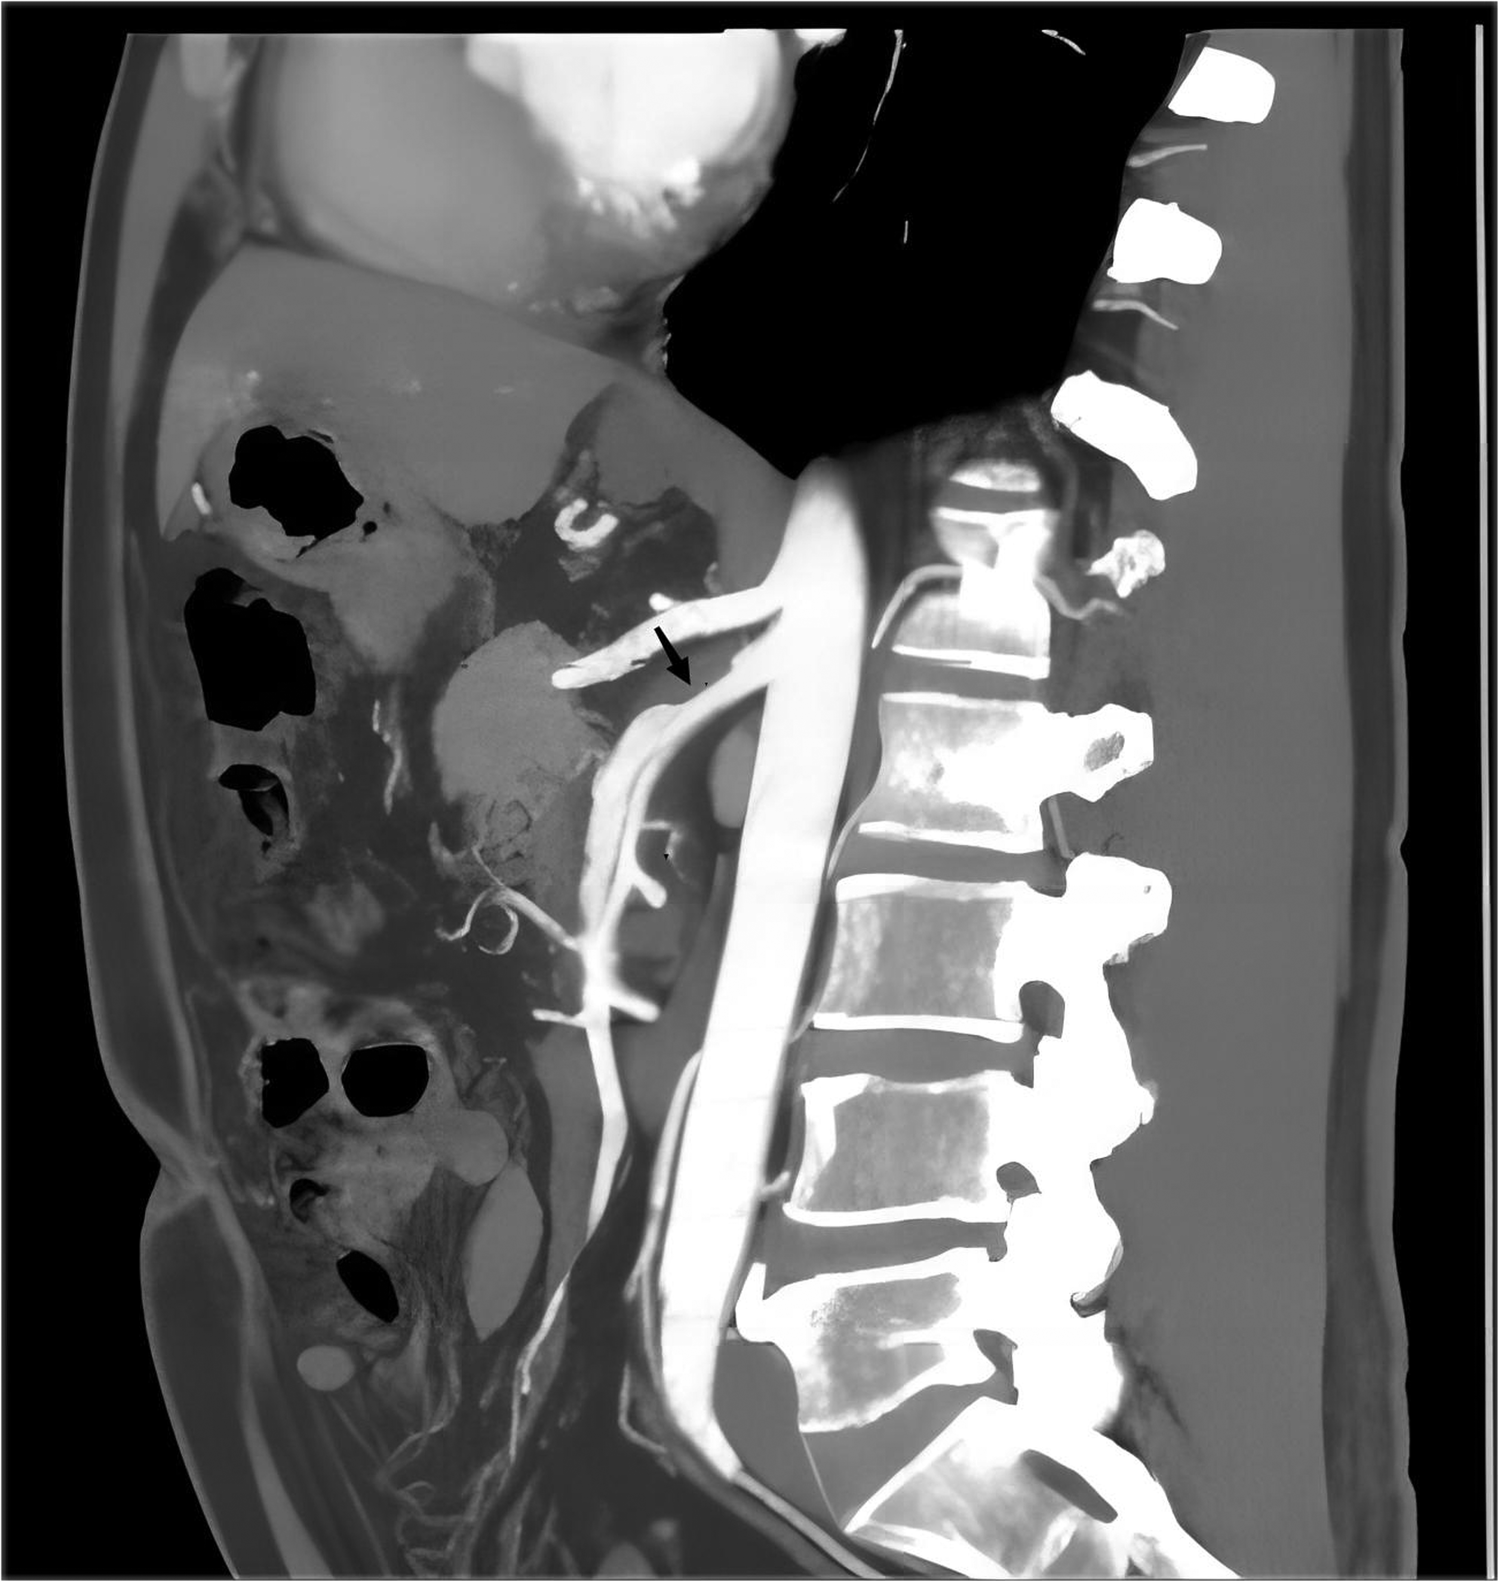

Figure 1

The typical performance of ISMAD in the sagittal plane of a computed tomography scan, with the black arrow pointing to the location of the dissection.